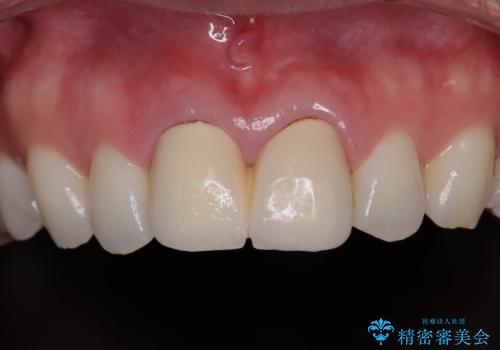

保険診療の黄ばんできた前歯をオールセラミッククラウンで自然な歯に